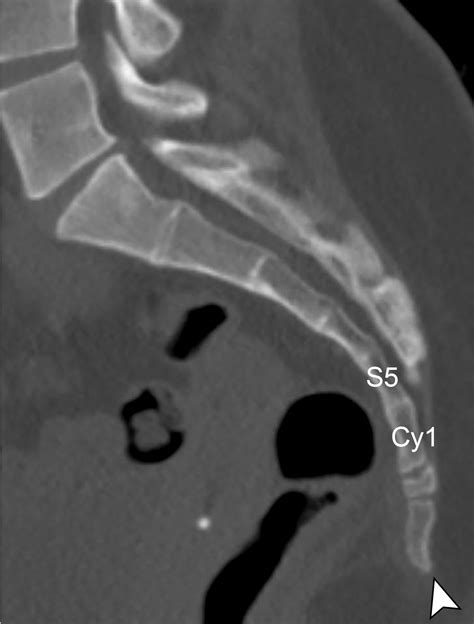

The sacrum and coccyx are essential components of the human spine. The sacrum is a triangular bone located at the base of the spine, formed by the fusion of five vertebrae. It connects the spine to the pelvis and plays a crucial role in supporting the body’s weight and facilitating movement. The coccyx, often referred to as the tailbone, is a small, triangular bone located at the bottom of the sacrum. It consists of three to five fused vertebrae and provides attachment points for various muscles and ligaments.

Interpreting Sacrum Coccyx X Ray results requires expertise in radiology. Healthcare professionals look for various signs and abnormalities in the images. Some common findings include:

• Fractures: Visible breaks or cracks in the sacrum or coccyx

• Dislocations: Misalignment of the sacrum or coccyx

• Degenerative changes: Wear and tear of the bones, often seen as bone spurs or narrowing of the joint spaces

• Tumors: Abnormal growths or masses in the bone

• Infections: Signs of bone infection, such as osteomyelitis

In some cases, additional imaging tests, such as MRI or CT scans, may be recommended for a more detailed evaluation.

• sacrum coccyx x ray anatomy